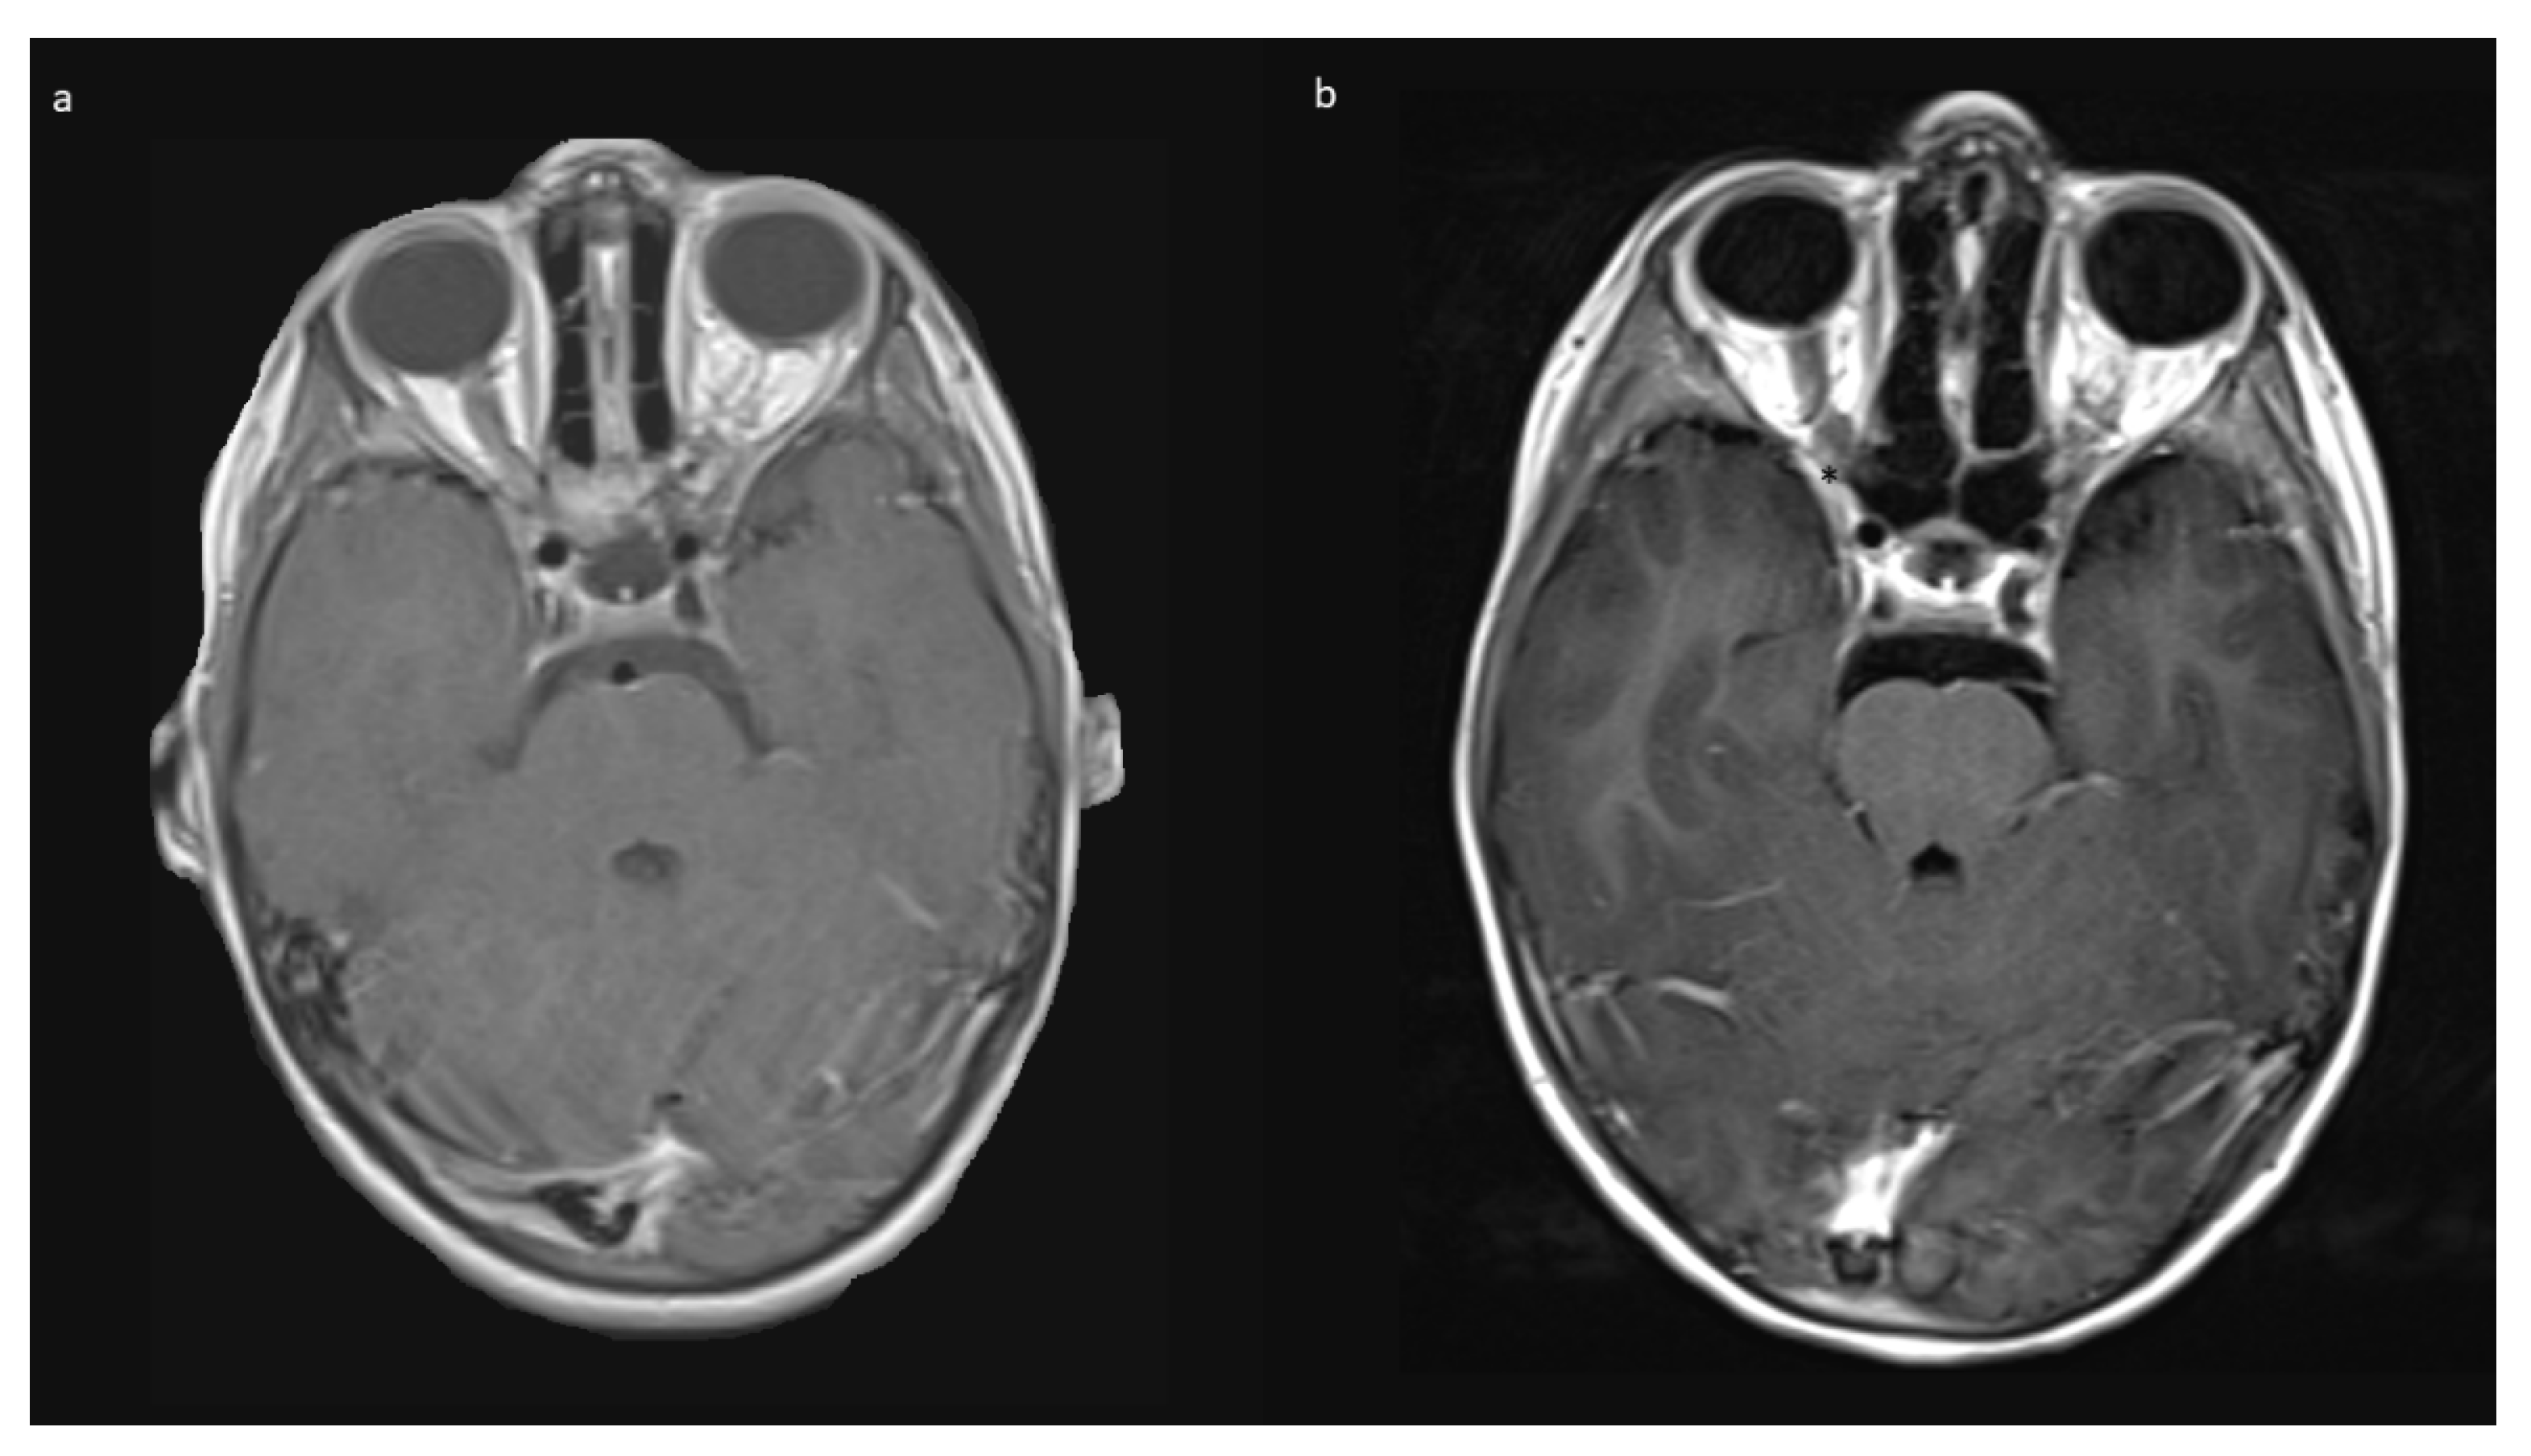

3.6. Follow-Up

The mean follow up was 42.0 (range 2–74) months in Group A, and 15 months in Group B. Patients received MRIs at 3 months post-surgery, then in cases of no residual tumor, every 6 to 12 months, depending on previous tumor growth velocity for up to 5 years. The case with unintended STR (No 1, Table 1) showed tumor progression in imaging and was subsequently treated with chemotherapy. No further growth was observed thereafter. In the two cases from Group B, there was stability of the intended residual optic nerve within the optic canal and no signs of tumor recurrence originating from there. In two of the four cases with NF1, a very small contralateral optic nerve glioma (MRI signal intensity changes and minimal contrast uptake, but no significant tumor extension) was known prior to surgery. Since in both children, no impairment of vision (visus 0.8 and 1.0) existed, this tumor manifestation was only observed in accordance with guidelines that asymptomatic tumors do not deserve treatment. An exemplary MR image set is provided in Figure 7.

Figure 7. Exemplary MR imaging follow-up of a small contralateral right-sided prechiasmatic optic nerve glioma (a) 12 months postoperatively; (b) 60 months postoperatively.